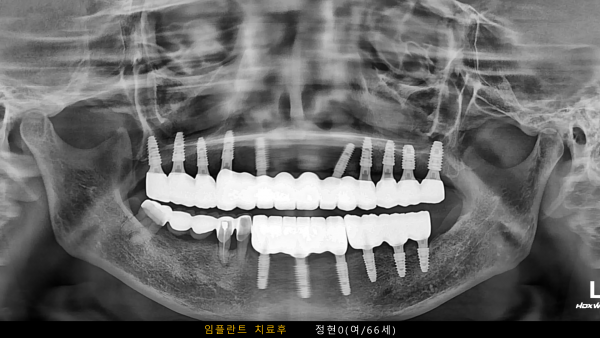

고난도 센터 | 여) 66세